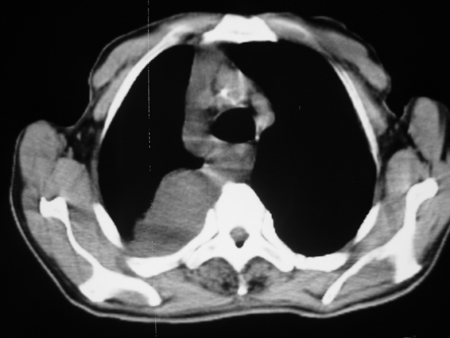

男77岁,胸痛就诊

右侧胸腔积液,部分包裹,右下肺膨胀不全,右下肺感染。

考虑右肺门占位并下叶不张 右胸包裹积液

右侧胸腔积液,部分包裹,右下肺膨胀不全

右肺中叶及下叶炎症并胸腔积液(部分包裹),建议抽液后复查ct除外占位。